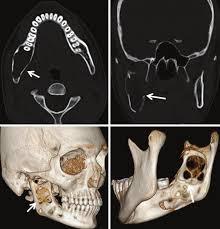

Cyst Diagnosis

Accurately identifies and locates cysts and other pathological lesions within the jaws and surrounding bone structures, aiding in proper treatment planning.

Cyst-Cross Sectional View

Cyst-Orthogonal Plane View